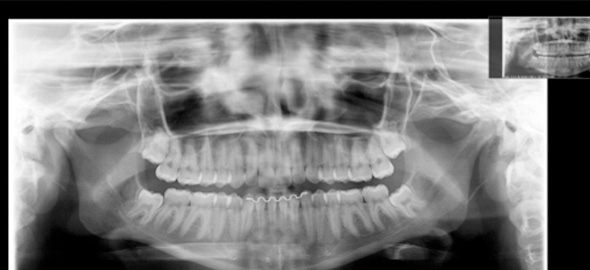

ORTODONTIA

A Ortodontia é a especialidade da Odontologia que diagnostica, acompanha, previne e trata os problemas relacionados ao crescimento, desenvolvimento e amadurecimento dos ossos da face, dos arcos dentários e da oclusão engrenagem dos dentes).

Esta especialidade que antigamente era indicada principalmente para os pacientes mais jovens, atualmente tem sua indicação muito mais ampla, tratando os pacientes adultos que querem se beneficiar dos resultados da ortodontia, como um sorriso mais alinhado e bonito, até aqueles que sofrem de alguma disfunção articular e os que precisam de tratamentos reabilitadores e estéticos.